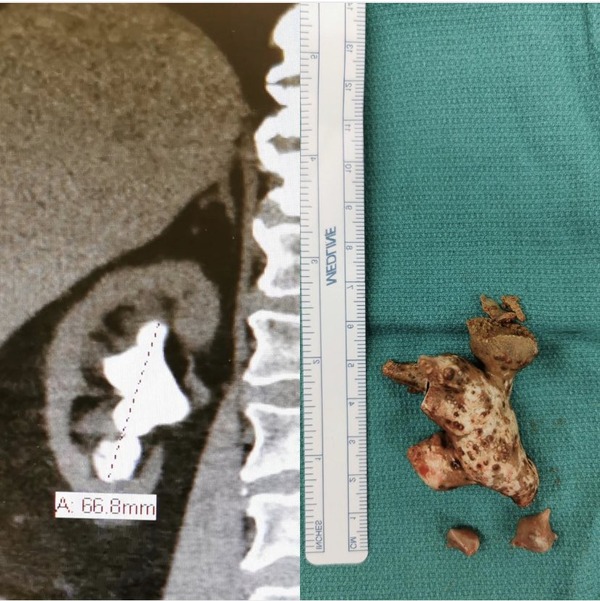

45: 以下、5ちゃんねるからVIPがお送りします 2020/11/27(金) 15:10:26.941 ID:1dFpAM7o0

すごい

no title

51: 以下、5ちゃんねるからVIPがお送りします 2020/11/27(金) 15:28:12.339 ID:pS5a1S+up

>>45

こんなんもう生姜だろ